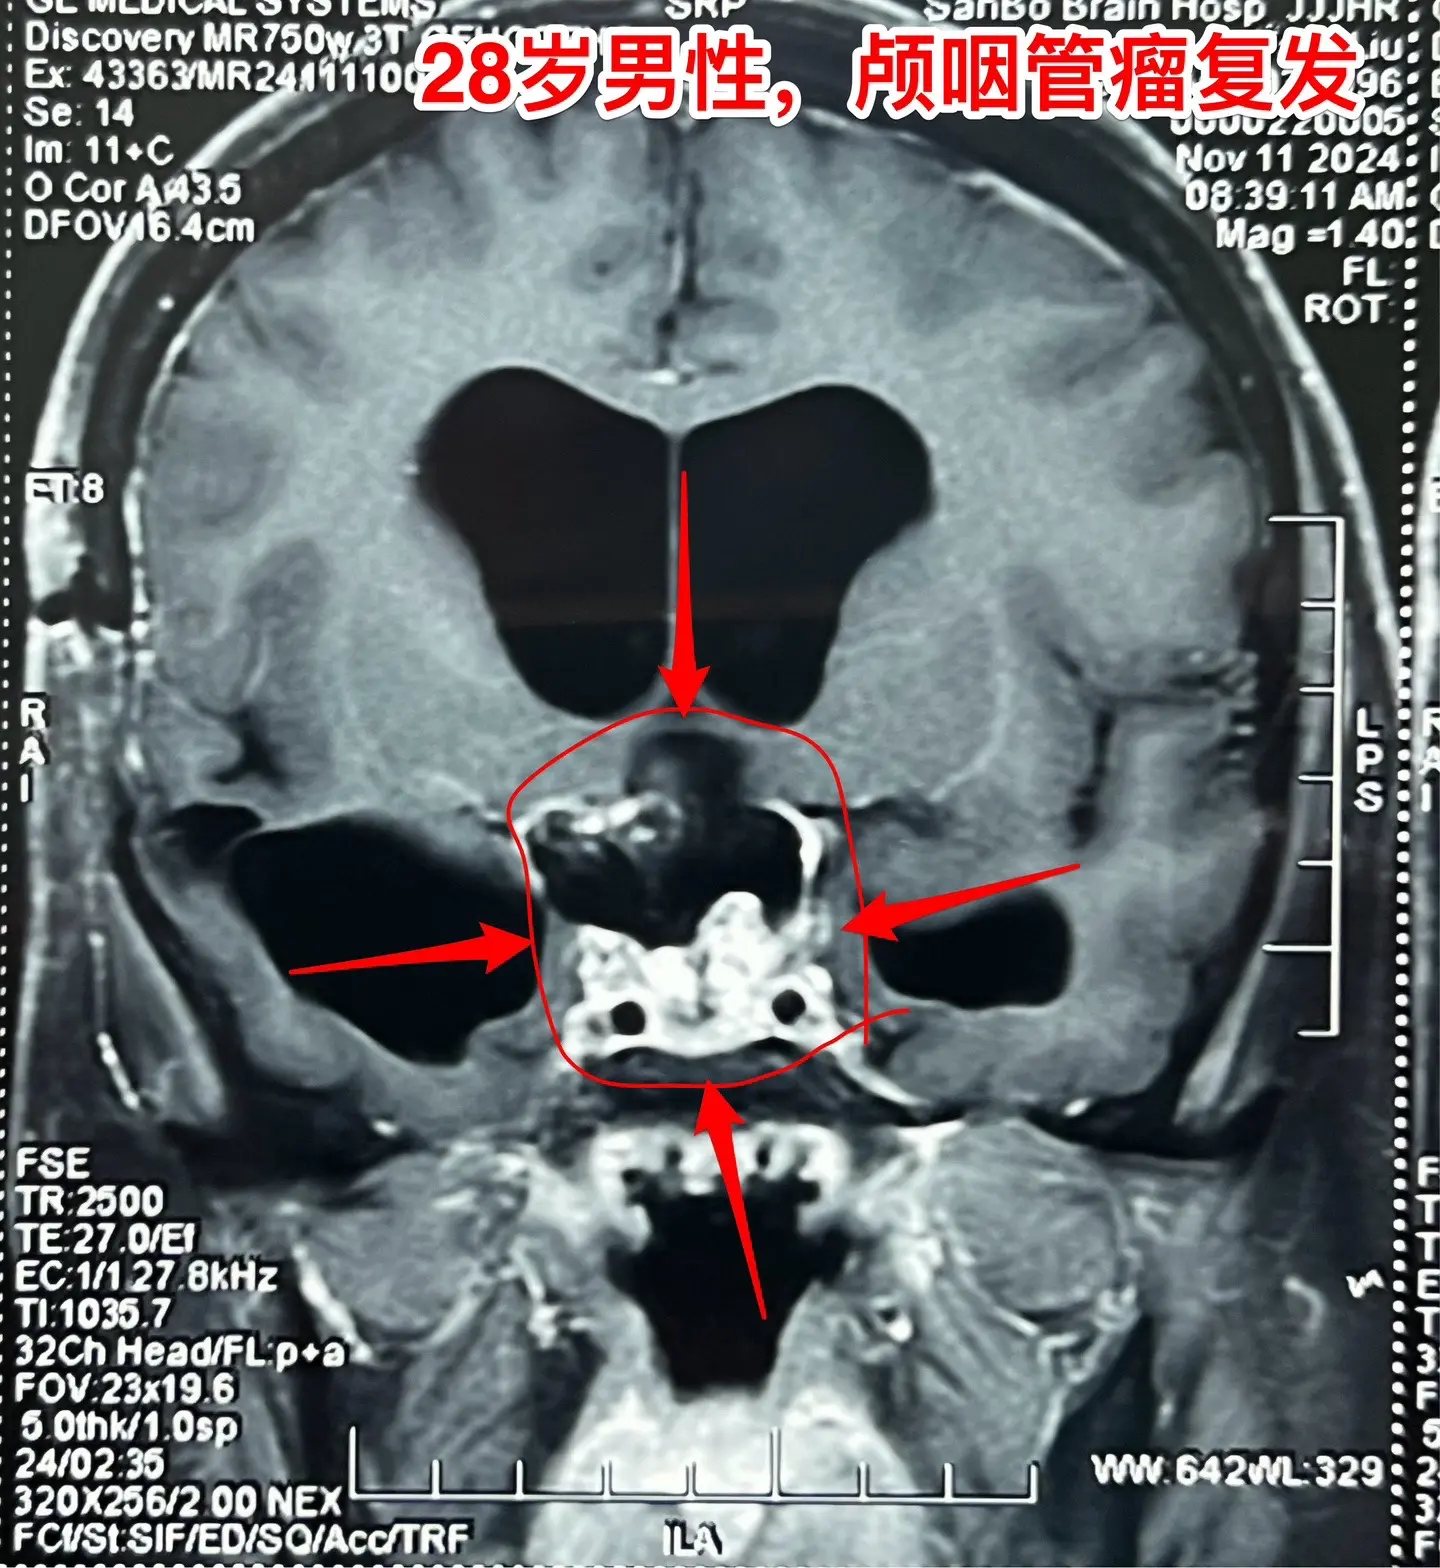

颅咽管瘤四次复发,为挽救视力只能作手术。28岁的四川小伙子,因颅咽管瘤在四川省先后作了四次开颅手术、一次脑室腹腔分流术。2024.6因肿瘤复发还作了一次伽马刀治疗,2024.9复查磁共振显示肿瘤体积在增大。 患者左眼已经失明了,右眼视力也在下降。为了挽救视力,他还是找我想再作一次手术,而且他的心态还是积极乐观的。 11月19日作了手术。原以为这个颅咽管瘤是不可能得到完全切除的,然而手术过程中却发现肿瘤不是一个整体,而是由四块肿瘤组成的,通过各个击破的方式将肿瘤完全切除了。病人右眼的视力也保住了。 希望肿瘤不再复发了!